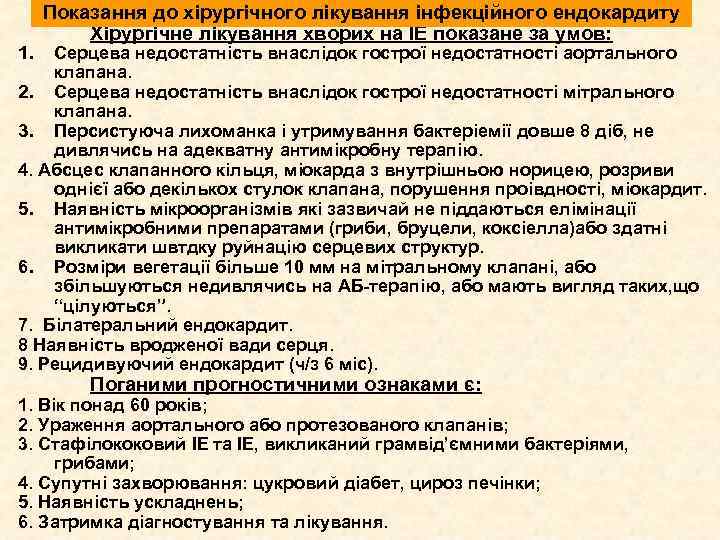

1. Показання до хірургічного лікування інфекційного ендокардиту Хірургічне лікування хворих на ІЕ показане за умов: Серцева недостатність внаслідок гострої недостатності аортального клапана. 2. Серцева недостатність внаслідок гострої недостатності мітрального клапана. 3. Персистуюча лихоманка і утримування бактеріемії довше 8 діб, не дивлячись на адекватну антимікробну терапію. 4. Абсцес клапанного кільця, міокарда з внутрішньою норицею, розриви однієї або декількох стулок клапана, порушення проівдності, міокардит. 5. Наявність мікроорганізмів які зазвичай не піддаються елімінації антимікробними препаратами (гриби, бруцели, коксіелла)або здатні викликати швтдку руйнацію серцевих структур. 6. Розміри вегетації більше 10 мм на мітральному клапані, або збільшуються недивлячись на АБ-терапію, або мають вигляд таких, що “цілуються”. 7. Білатеральний ендокардит. 8 Наявність вродженої вади серця. 9. Рецидивуючий ендокардит (ч/з 6 міс). Поганими прогностичними ознаками є: 1. Вік понад 60 років; 2. Ураження аортального або протезованого клапанів; 3. Стафілококовий ІЕ та ІЕ, викликаний грамвід’ємними бактеріями, грибами; 4. Супутні захворювання: цукровий діабет, цироз печінки; 5. Наявність ускладнень; 6. Затримка діагностування та лікування.